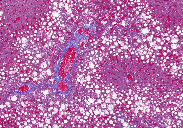

1、HE染色

5、油红 o 染色